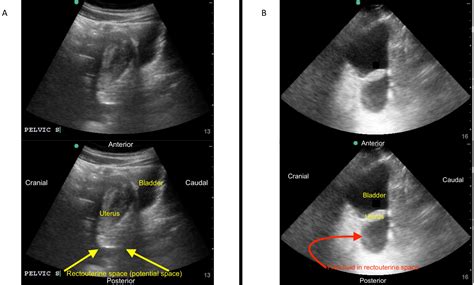

• EFAST (Extended Focused Assessment with Sonography for Trauma): This is a comprehensive ultrasound examination used to evaluate patients with trauma. It includes views of the heart, lungs, abdomen, and pelvis to detect fluid collections, pneumothorax, and other injuries.

• Trauma Assessment: In trauma patients, the Fast Exam Ultrasound helps identify internal injuries, such as hemoperitoneum, hemothorax, and pericardial effusion.

• Pathological Findings: Look for signs of pathology, such as fluid collections, organ abnormalities, and other conditions.